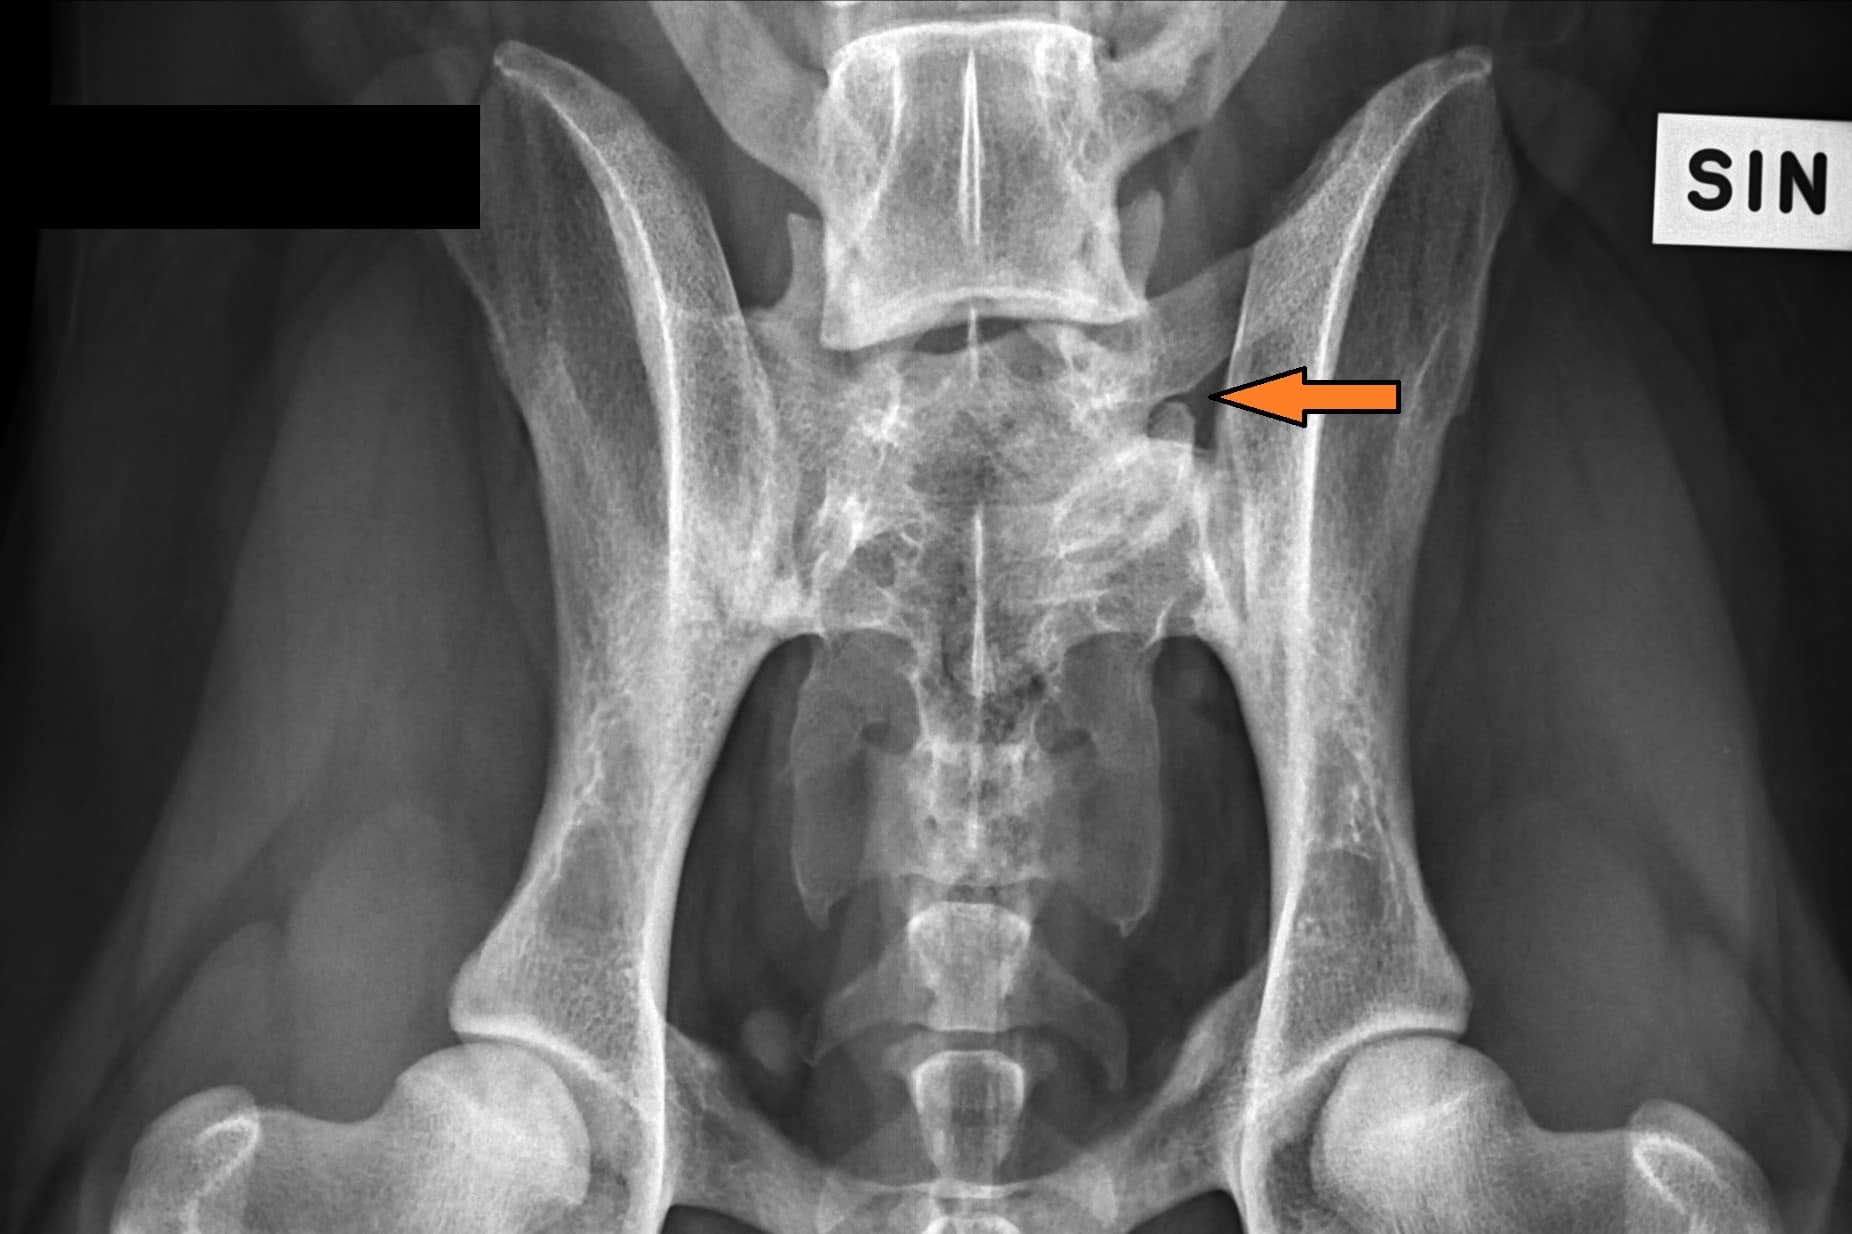

LTV3; asymmetrical; on the right in the VD photo the left side of S1 is shaped like a sacral vertebra and on the right side S1 is shaped like a lumbar vertebra including the spinous process.

The asymmetrical form, LTV3, seems to be a bit more tricky than the other forms. In some cases asymmetrical form comes with rotated pelvis, which might lead to unilateral development in hips. This is actually very logical; when the pelvis is not straight and in balance there will be uneven bear of weight between hips. In long term this uneven state might cause the worse hip wear sooner than the better hip and lameness and osteoarthritis may occur.

In the Finnish Kennel Club’s database 38,9% of Rhodesian Ridgebacks with LTV3 have one hip scored 1-2 degrees lower than the other one, ie. A/C (Oct 2020). The score doesn’t tell if the dog’s pelvis is straight or rotated.

“Asymmetrical LTV favours pelvic rotation over its long axis, resulting in inadequate femoral head coverage by the acetabulum on one side. Inadequate coverage of the femoral head favours subluxation, malformation of the hip joint, and secondary osteoarthritis. Asymmetrical hip conformation may therefore be the sequela of a LTV and mask or aggravate genetically induced canine hip dysplasia.”

(Flückiger M., Frank Steffen F. et al 2017)